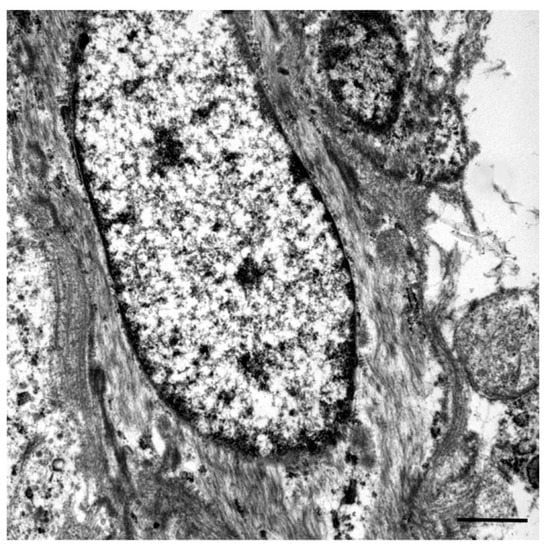

A Recurrent Inflammatory Myofibroblastic Tumor-like Lesion of the Splenic Capsule in a Kitten: Clinical, Microscopic and Ultrastructural Description

2. Case Presentation